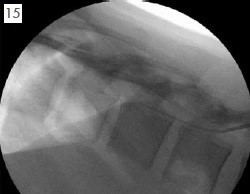

脊椎內給藥系統簡介